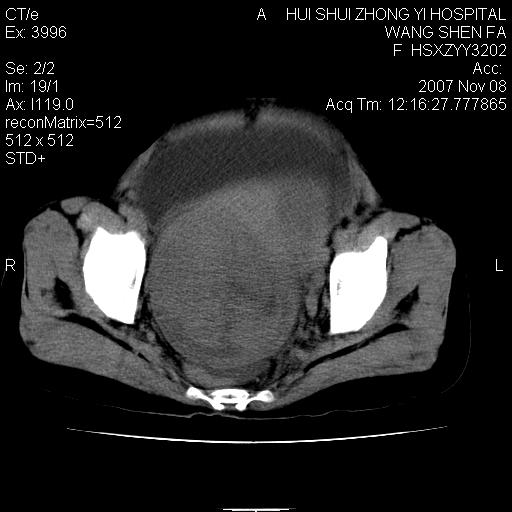

标题: CT10389:女,38岁,腹部巨大包块 [打印本页]

标题: CT10389:女,38岁,腹部巨大包块

腹部巨大包块半年,质硬,边界不清。

腹腔及盆腔内可见巨大软组织肿物影,内部密度欠均匀,边界尚清晰,周围组织受压移位明显,右侧输尿管受压明显,上端扩张肾盂轻度积水,病灶外形分叶明显,似多个肿物融合而成。考虑来源于间叶组织的恶性肿瘤可能性大

下腹部巨大软组织影,密度不均匀,并可见分隔,病灶边缘较清,肠管受压移位。子宫未显示。盆腔、双侧腹股沟未见明显肿大淋巴结。考虑:1.卵巢病变可能性大,囊腺癌>卵巢癌>囊腺瘤.2.多发性阔韧带子宫肌瘤待除外.

腹腔及盆腔内可见巨大软组织肿物影,内部密度欠均匀,边界尚清晰,周围组织受压移位明显,膀胱前上移位,右侧输尿管受压明显,上端扩张肾盂轻度积水。考虑:1卵巢病变可能性大,囊腺癌>卵巢癌>囊腺瘤.2 子宫病变,子宫肌瘤?